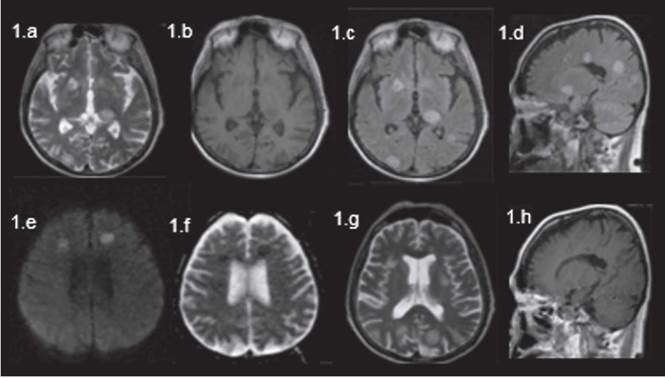

Imágenes de resonancia magnética nuclear en equipo de 1,5 UT con cortes axial en eco spin para T2 (a), coronal T (b), sagital flair (C), axial T1 post- contraste (D) axial flair (e), correlación en cortes tomográficos (f,g), corte axial tomográfico en parénquima pulmonar (h) identificando lesiones de alta intensidad de señal en T2 y flair, baja señal en T1 con restricción de la difusión sin actual captación de contraste, que en correlación tomográfica se representan con lesiones hipodensas focales edematosas múltiples y con curso clínico de nódulos parenquimatosos pulmonares concomitantes.

Figura 2: Imágenes de resonancia magnética nuclear en equipo de 1,5 UT con cortes axial en eco spin para T2 (a), coronal T (b), sagital flair (C), axial T1 post- contraste (D) axial flair (e), correlación en cortes tomográficos (f,g), corte axial tomográfico en parénquima pulmonar (h) identificando lesiones de alta intensidad de señal en T2 y flair, baja señal en T1 con restricción de la difusión sin actual captación de contraste, que en correlación tomográfica se representan con lesiones hipodensas focales edematosas múltiples y con curso clínico de nódulos parenquimatosos pulmonares concomitantes.

Los estudios de RM cerebral del caso en estudio mostraron innumerables lesiones redondeadas de baja señal en secuencias potenciadas en T1 y alta señal en secuencias potenciadas en T2 y FLAIR, que comprometían tanto la fosa posterior como la región supratentorial, de predominio subcortical y en sustancia blanca, algunas de ellas también en núcleos de la base de ambos hemisferios y en la región talámica izquierda con diámetros entre 5 y 19 mm, y solo algunas de ellas presentaron un sutil realce en anillo sin edema perilesional, con alta señal en las secuencias de difusión y baja señal en los mapas de ADC.